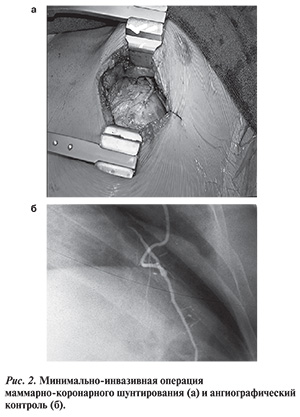

В связи с необходимостью выполнения стернотомии и кожных разрезов нижних конечностей для забора вен пациенты не понимают уменьшенной инвазивности операции OPCAB и предпочитают процедуры повторного стентирования. Парадокс современной хирургической реваскуляризации методом OPCAB состоит в том, что пациентам предлагается инвазивная процедура с применением субоптимальных аутовенозных шунтов [5, 14], схожих по эффективности со стентами с лекарственным покрытием. В то же время хорошие отдаленные результаты операции КШ в значительной степени связаны с качеством шунта ЛВГА-ПНА, отличающимся долговечностью [15], который может быть выполнен через щадящий доступ без разреза грудины и без остановки сердца (рис. 2) с тем же уровнем качества анастомоза, как и при ИК [11]. Обширные данные литературы подтверждают отличные ангиографические и клинические результаты операции MIDCAB [7, 8, 16, 17].